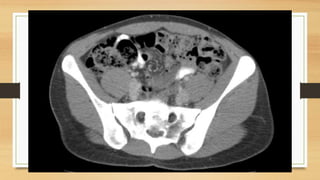

Este documento trata sobre fracturas de pelvis y acetábulo de tipos I y II. Explica la anatomía de la pelvis, incluyendo huesos, ligamentos y vasos. Describe la epidemiología, clasificación y diagnóstico de fracturas de pelvis. Detalla abordajes quirúrgicos, técnicas de osteosíntesis y fijación externa para el tratamiento de fracturas de pelvis. Finalmente, cubre posibles complicaciones.